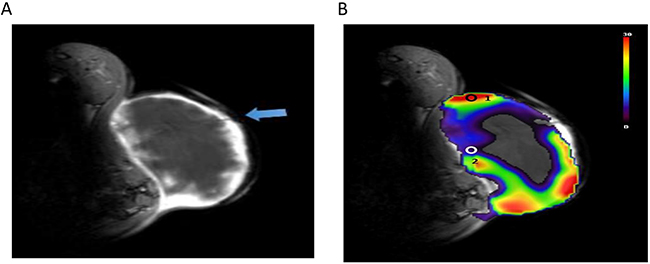

To validate the role of PSIC in hypoxia measurement, we used OxyLite probes to measure the change in pO2 (ΔpO2) in the tumors. OxyLite probes were placed in the solid tumor and penumbra areas. The OxyLite probes had slight hypointensity on T1-weighted images (Figure 7A). The PSIC map of one representative subcutaneous tumor with ROI placement is shown in Figure 7B. The OxyLite probe measuring point of penumbra area was mainly located in the hypoxia region (PSIC<10%) delineated by OE-MRI; and measuring point of solid tumor was mainly located in the normoxia region (PSIC>10%) delineated by OE-MRI.

Figure 7: PSIC maps of a representative subcutaneous tumor. (A) Gadolinium-enhanced T1-weighted MR image. The blue arrow indicates OxyLite probes. (B) PSIC maps of a representative subcutaneous tumor. Circles represent ROIs; circle “1” indicates the tumor-ROI, and circle “2” indicates the penumbra-ROI.